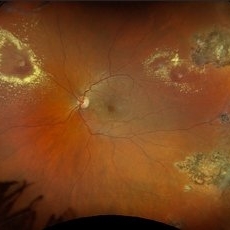

Retinal Aneurysms

Retinal Aneurysms

Aug 6 2025 by Korey Starkey

54 year-old patient presents with scattered peripheral aneurysms with exudates. FA was performed showing peripheral nonperfusion and aneurysms. Treated patient with PRP and focal laser to aneurysms and continued observation.

Photographer: Kore Starkey

Imaging device: Optos

Condition/keywords: aneurysm, branch retinal vein occlusion (BRVO), chorioretinal scar, circinate ring, exudates, fundus photography, lesion, Optos, retinal aneurysms